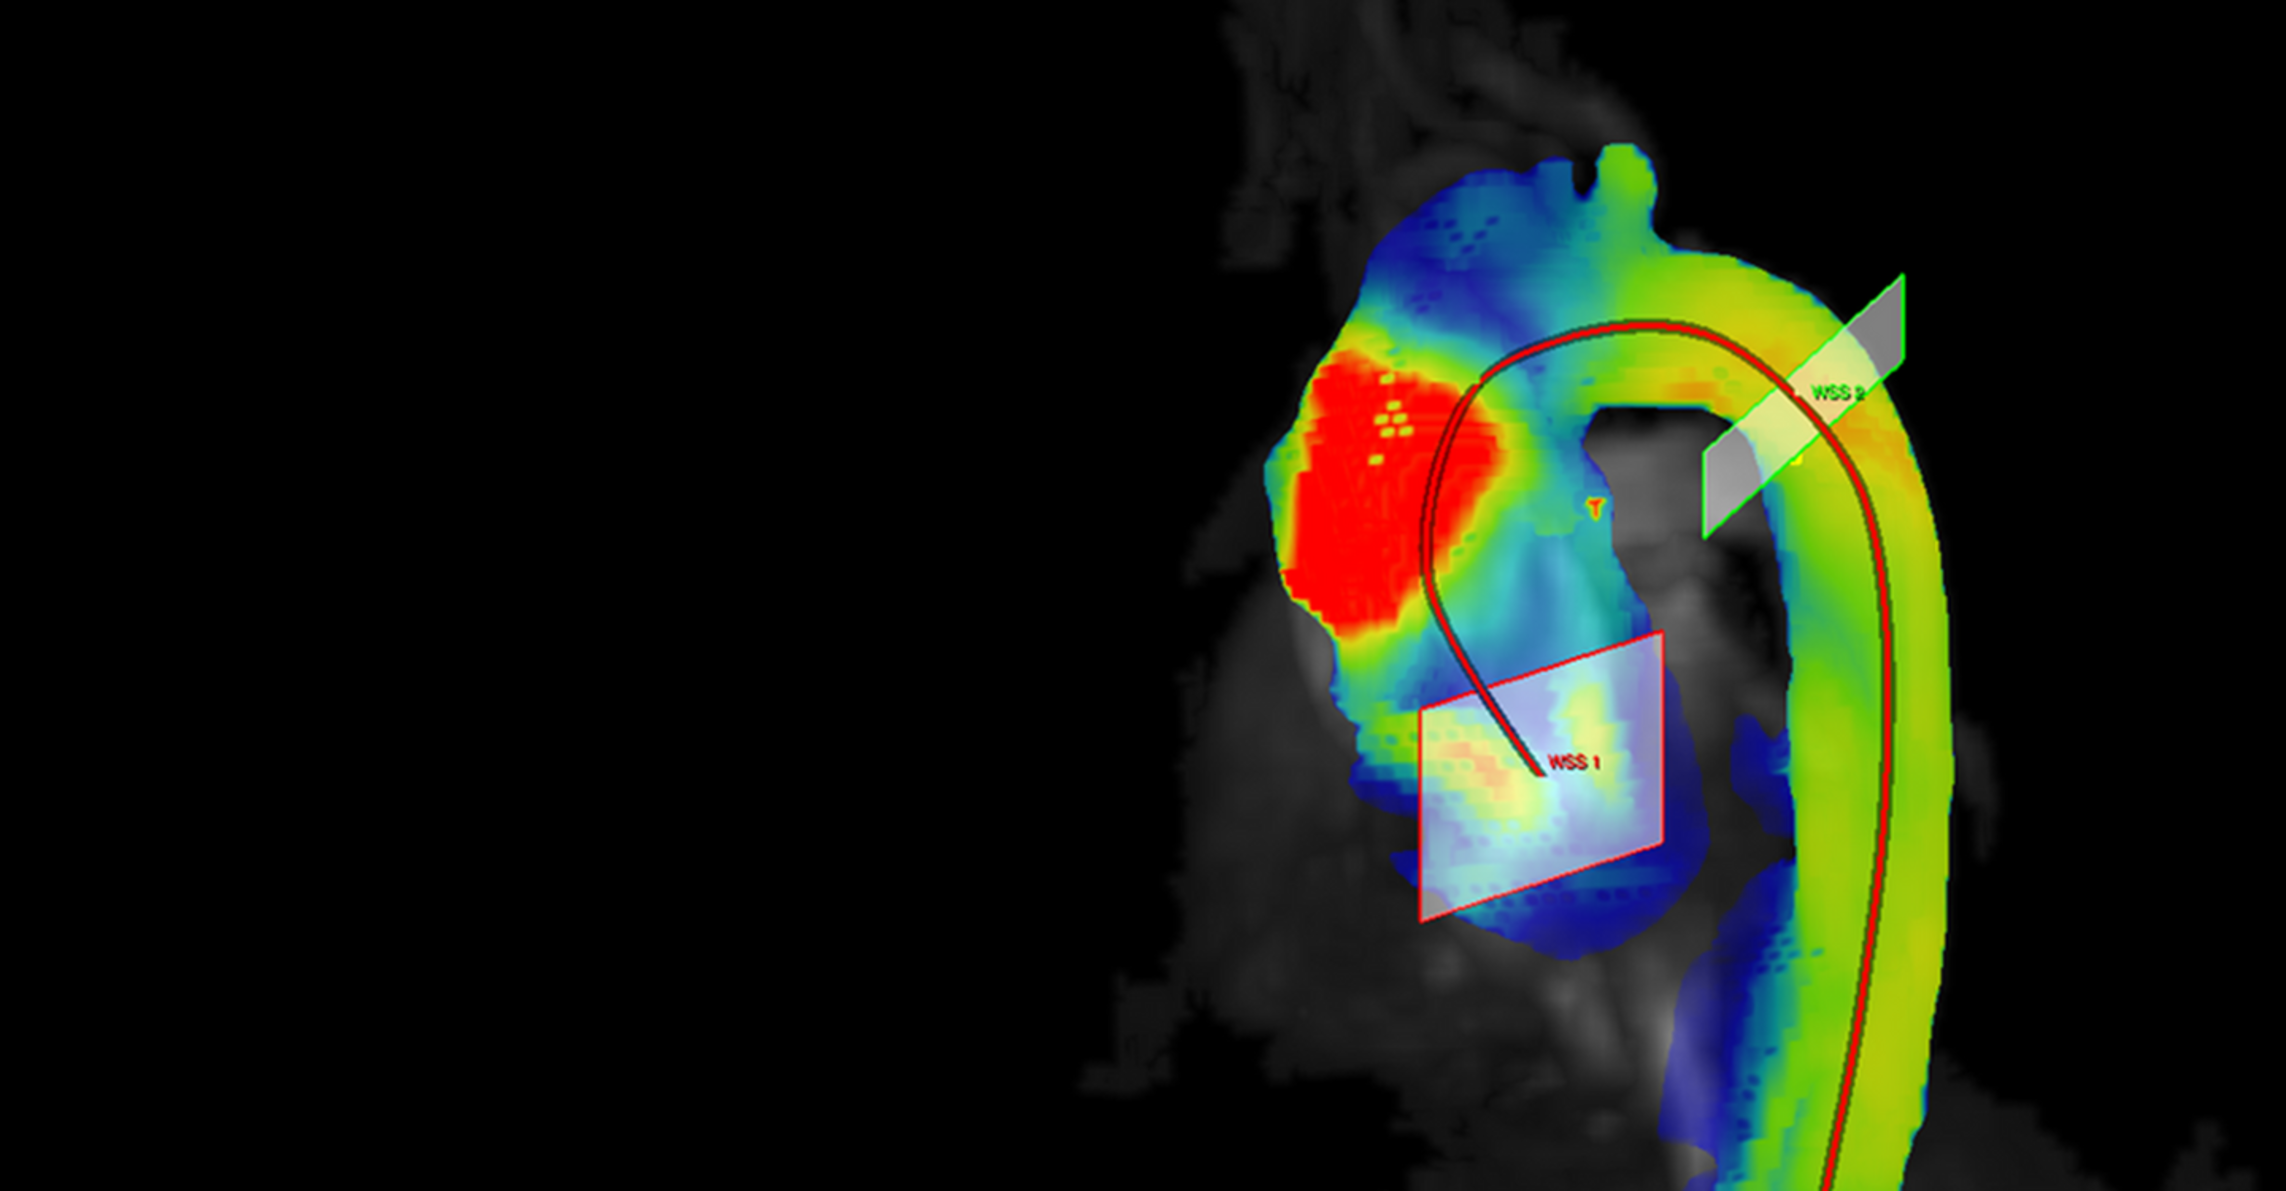

The ECRC researcher is currently working on several projects. One objective of her team is to visualise blood flow through vessels; she and her colleagues are working with high-performance devices with a field strength of up to 7 tesla. Schulz-Menger also hopes to investigate more closely heart muscle damage, such as that caused by chemotherapies in cancer treatment or that results from muscular dystrophies. She is thankful that the ECRC offers much time and space for application-oriented research that usually benefits the patient quickly.